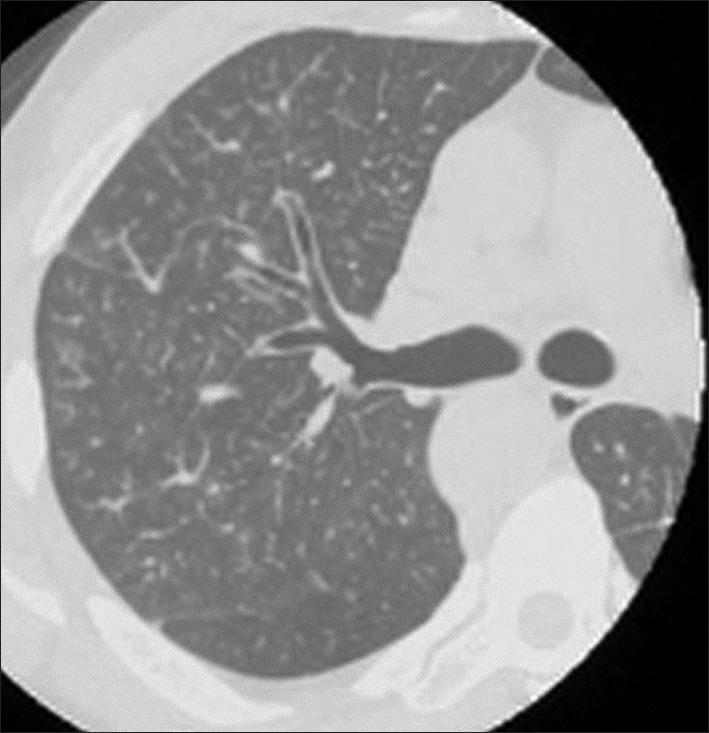

由胃癌引起的肺肿瘤血栓性微血管病。

Pulmonary tumor thrombotic microangiopathy caused by gastric cancer.

Pulmonary tumor thrombotic microangiopathy (PTTM) is a fatal cancer-related pulmonary complication with rapidly progressing dyspnea, and occasionally induces sudden death. Here, we describe a postmortem-diagnosed PTTM case caused by gastric cancer, with the complaint of progressing dyspnea for 5 days.He did not have any abdominal symptoms or cancer history. PTTM should be considered in patients with rapidly worsening respiratory conditions, even if there is no cancer history.

肺肿瘤性血栓性微血管病(PTTM)是一种致命的癌症相关肺部并发症,表现为进行性呼吸困难,偶尔导致猝死。在此,我们描述了一例由胃癌引起的尸检确诊的 PTTM 病例,该患者的主要表现为进行性呼吸困难 5 天,并无任何腹部症状或癌症病史。对于呼吸状况迅速恶化的患者,即使没有癌症病史,也应考虑 PTTM 的可能。